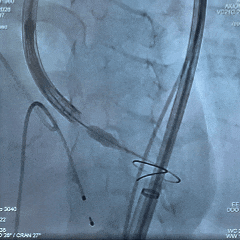

瓣膜0位初始定位释放,展开过程微微下移

全展开位造影评估

瓣膜呈直筒型,微腰,大弯侧约瓣下3mm,少量反流,冠脉显影

瓣膜无张力脱钩

植入后造影评估

瓣膜位置合适,可见少量反流

多角度造影评估

瓣膜形态可,冠脉显影,猪尾测量压差为0